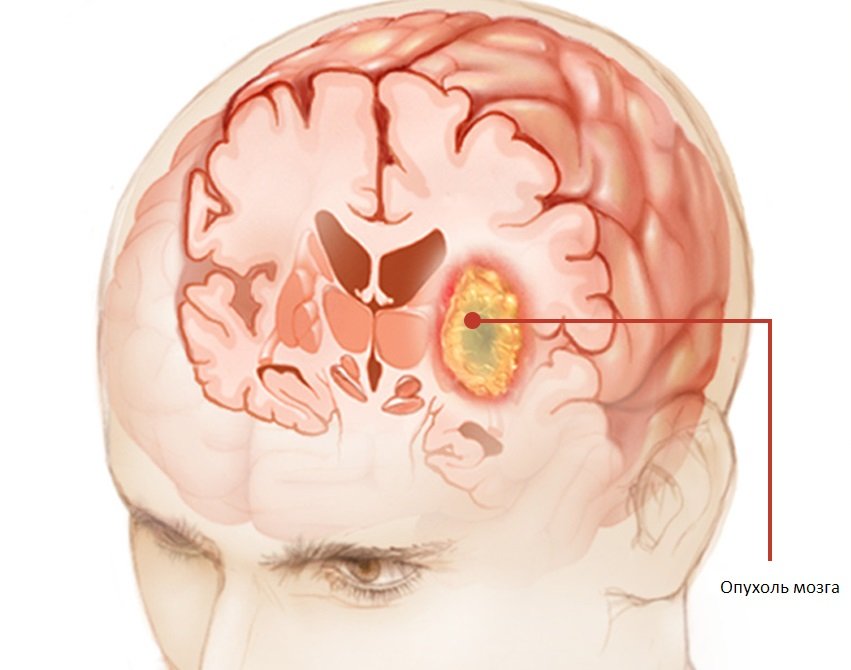

Деление опухоли по гистологии выявляет около 120 видов. Любой из этих видов характеризуется своими индивидуальными особенностями: строение, скорость развития, область локализации, размер (от 2 до 6 см). Но все их объединяет один факт – они образуются внутри черепной коробки и неопластический процесс происходит там же – в ограниченном пространстве, то есть являются «плюс»- тканью внутри черепной коробки.

Развиваясь внутри черепной коробки опухоль, разрастаясь, меняет свои размеры, начинает «пухнуть» и сдавливать расположенные рядом структуры. Эта их особенность и объединяет все эти виды в одну группу.